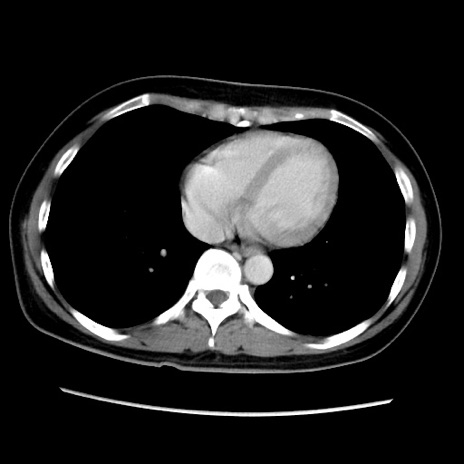

症例39(横断像)

【症例】40歳代女性

【主訴】上下腹部痛

【現病歴】2日目から下腹部痛あり。夜間は痛みで眠れなかった。昨日より上腹部痛と下痢が出現。臥位で痛みは軽快したため、休んでいた。本日になって臥位でも立位でも痛みが強くなってきたため救急要請。

【既往歴】子宮内膜症

【身体所見】部:平坦・軟、左上下腹部に圧痛あり、反跳痛あり。

【データ】WBC 21800、CRP 26.78